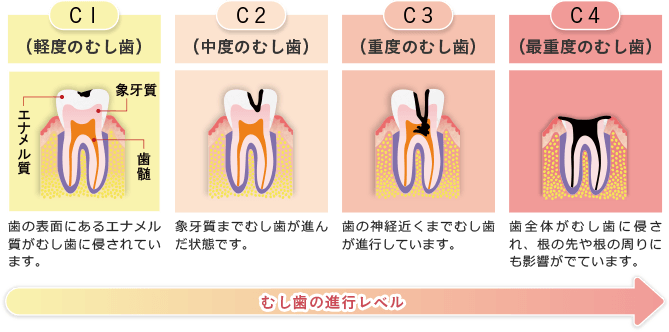

むし歯治療

患者様のむし歯の進行状態をしっかりと診断してから治療に入ります。

初期のむし歯であれば、詰め物をすることで比較的簡単に治療できますが、進行が進み重度のむし歯になると、神経の治療や抜歯の必要が出てきたり、全身にも悪影響を及ぼすことがあります。